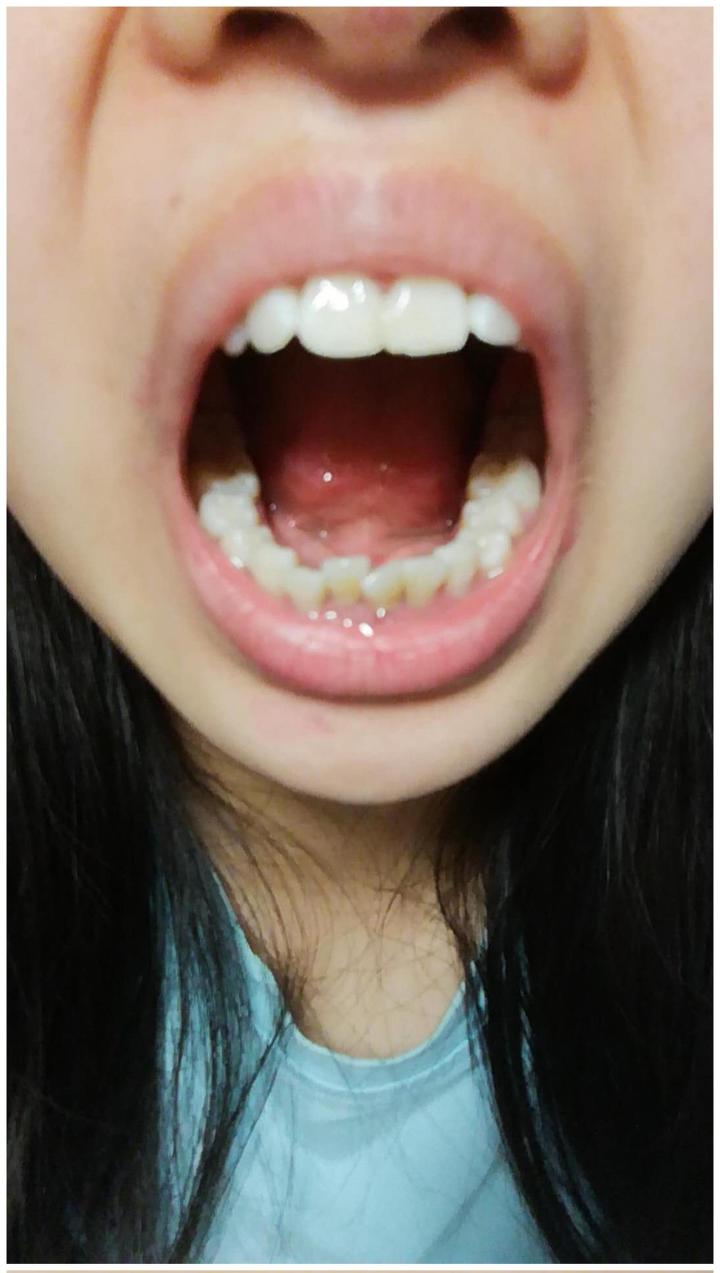

我的上排牙有些突出,就是大家平时说的龅牙T^T。。。下排牙就是有些乱,好吧,这么看起来其实挺乱的= =。。医生给我的诊断是牙列不齐且拥挤,左侧为近中关系,前突。我真的不能再忍我这口丑丑的牙了呜呜呜!!后来,和医生确定方案,又等了一段时间,终于拿到了我的牙套。

这是我刚戴上第一幅牙套的时候拍的照片,凑近才能看这么清楚,平时可是看不出来的。